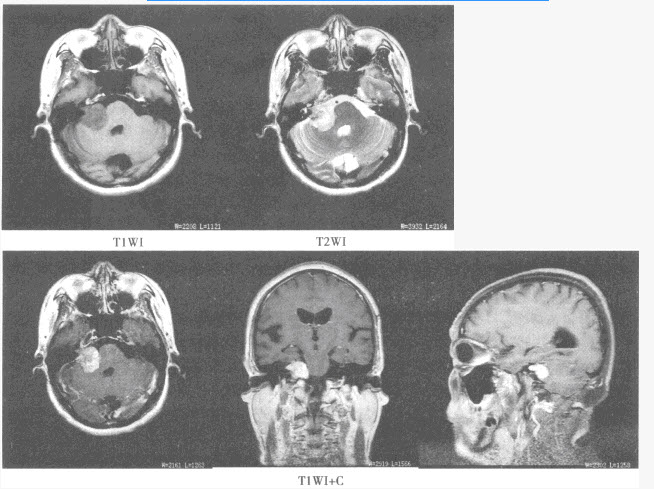

患者,男性,79岁,上腹部疼痛,不易缓解,吐咖啡色血液。行上腹部CT增强扫描,如下图